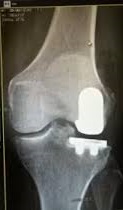

Parlo per esperienza diretta e dopo aver visto che le sue lastre sono identiche alle mie. La testa della tibia è stata piallata per poter inserire un piatto di sostegno ad uno spessore di plastica che fa le veci della cartilagine. Sulla testa del femore è stato inserito un cavallotto tondo a copertura. Questi due inserti sono fissati nelle ossa mediante perni. Ecco, questi perni, in caso di incidente serio, possono frantumare le teste del femore e tibia.

Da un articolo d Humanitas

Gli sportivi che praticano discipline invernali in modo agonistico possono sperare di tornare a gareggiare ad alto livello? «Sì, come ho accennato prima, con la dovuta riabilitazione e preparazione le abilità possono essere recuperate. Nel caso di protesi all’anca si può tornare al 100%, mentre un po’ più bassa è la percentuale che riguarda il ginocchio. Bisogna però sempre ricordare che essendoci un corpo estraneo – la protesi – le probabilità di infortunio sono molto più alte. Soprattutto, c’è il rischio di incorrere in fratture peri-protesiche: l’osso che si trova attorno alla protesi corre un rischio maggiore di fratturarsi rispetto alla stessa porzione di osso della persona senza protesi».

Le immagini qui sotto le aveva pubblicate la Vonn sulla sua pagina FB (cambia la gamba ma sono identiche alle mie)

Immagine:

15,11 KB

9,06 KB |